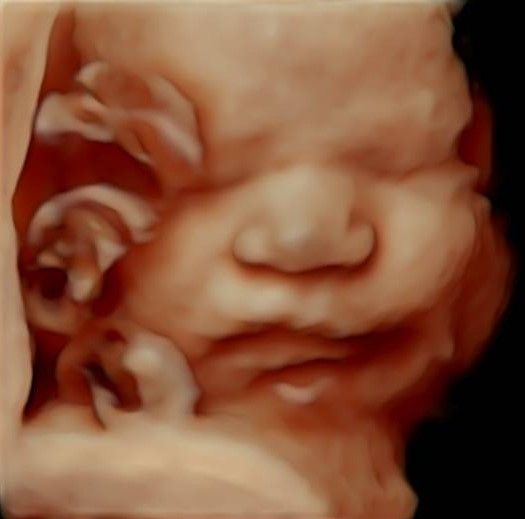

Eseguo in particolare ecografie ostetriche e ginecologiche anche in 3D e 4D per meglio identificare la problematica, offrire diagnosi precise ed un trattamento mirato e personalizzato.

• Arcispedale Santa Maria Nuova - IRCSS Reggio Emilia ecografia ostetrica 3D/4D  •